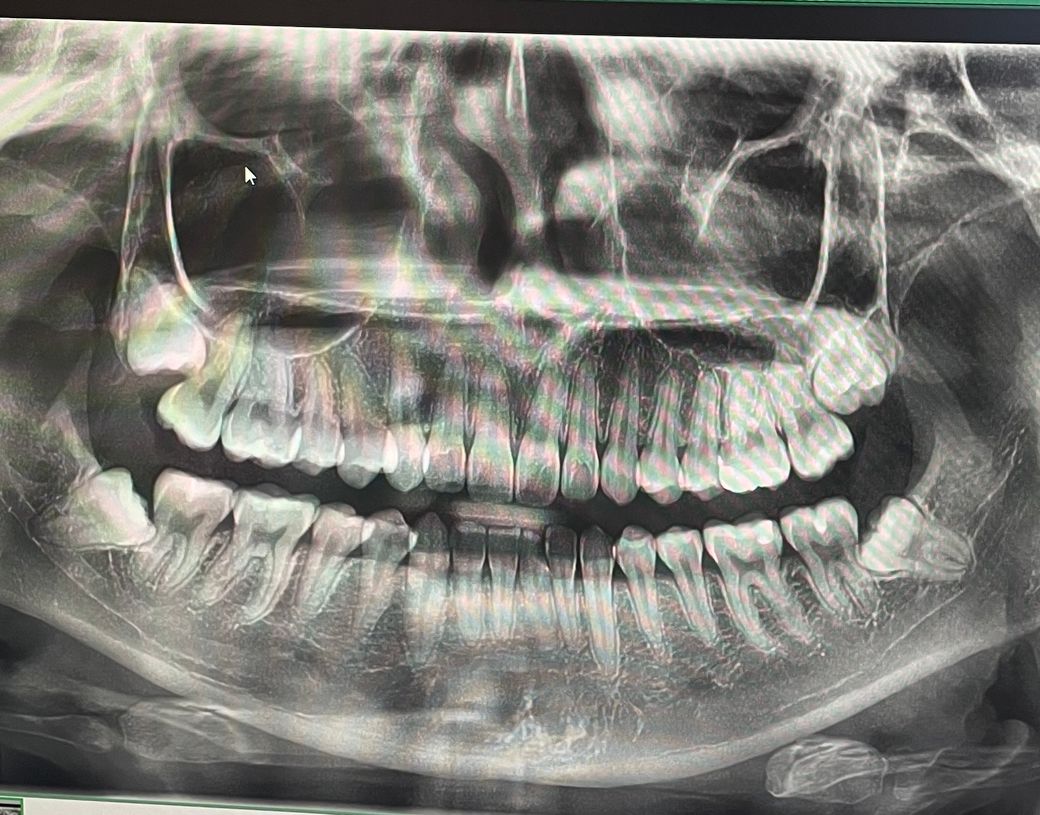

아래쪽 사랑니들이 옆 어금니 뿌리 쪽을 파고든것처럼 보이는데 파고들어있는게 맞는지 아니면 맞물려있지 않고 따로따로 존재하는건지 궁금해 질문 드립니다!

그리고 사랑니가 아직 다 나지 않았는데 지금 당장 발치할 필요는 없는게 맞나요?

엑스레이 상으로 보면 사랑니는 매복상태인거 같습니다. 별다은 이유가 없다면 발치를 하지 않으셔도 될것같습니다.

파고들어간건지 등은 3차원적인 영상인 CT를 통해서만 파악할 수 있으며 빼는 게 좋아보이는 위치입니다.

사랑니가 잇몸 안에 들어 있고 큰 문제를 발생시키지 않는다면 굳이 무리해서 발치를 할 필요는 없습니다 사진상으로 봤을 경우에는 사랑니가 큰 문제가 없이 있는 것으로 보입니다.

현재 사랑니가 앞의 어금니에 영향을 미치고 있기에 조금더 지켜보다가 빠른시일내에 발치를 하는 것이 좋습니다.